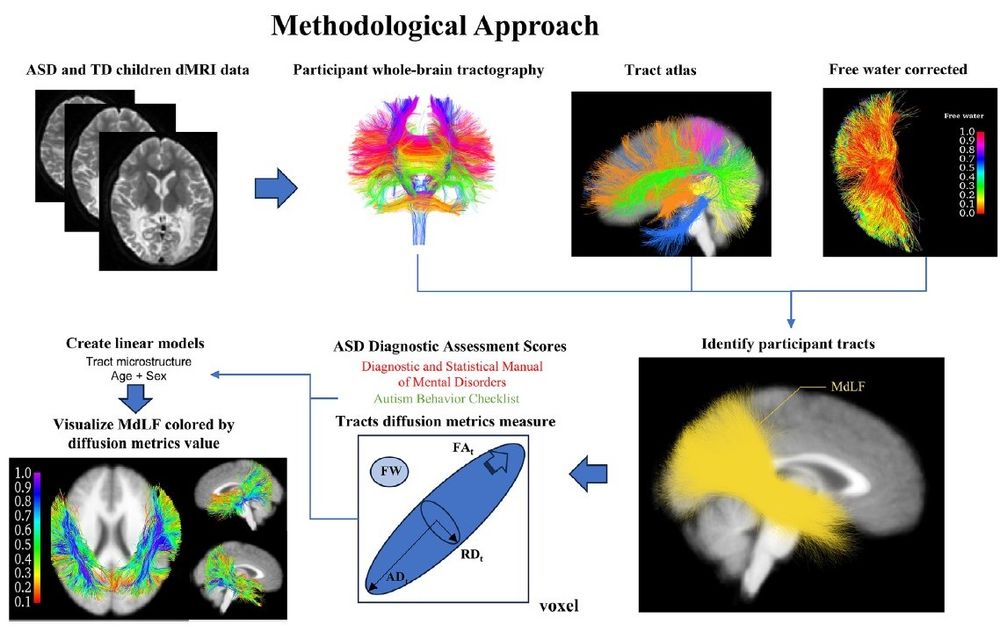

onlinelibrary.wiley.com/doi/epdf/10....

#neuroimaging #neurology #neuroskyence #radiology #BrainDevelopment #DiffusionMRI #LanguageImpairment #Autism

onlinelibrary.wiley.com/doi/epdf/10....

#neuroimaging #neurology #neuroskyence #radiology #BrainDevelopment #DiffusionMRI #LanguageImpairment #Autism